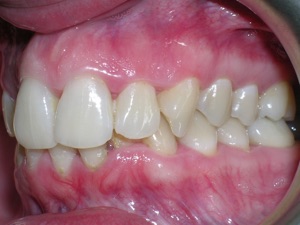

This case was of a young lady who desperately wanted Invisalign, but had been told it was not possible. There was not one, but two teeth that had come in toward the roof of the mouth.

Here are some progress photos.

Needless to say, we were both quite happy with the outcome. Using elastics we were able to push back the back teeth and create space for the two teeth stuck behind.